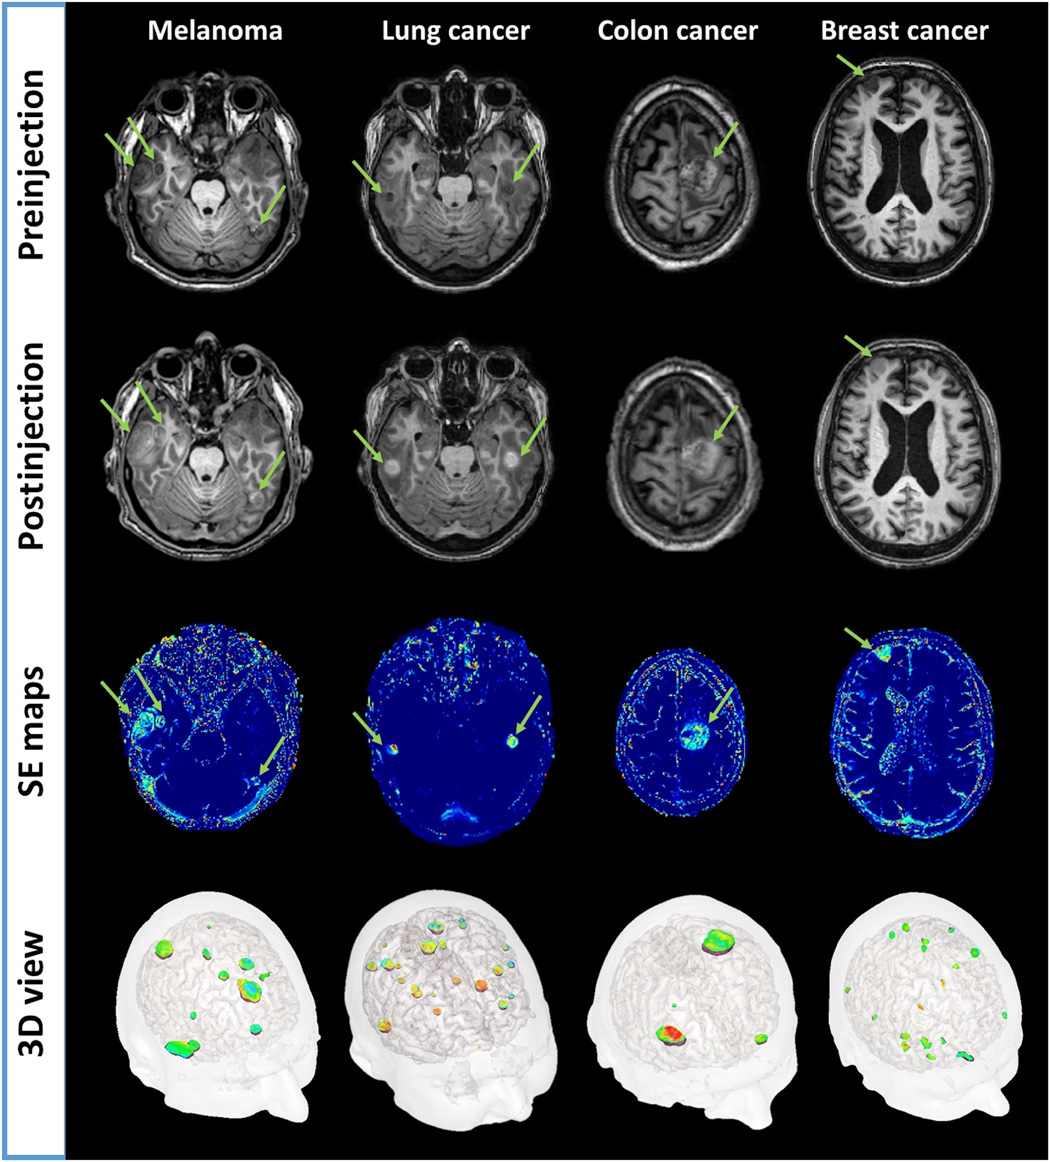

Two hours after AGuIX injection, MRI signal enhancements (SEs) were observed for all measurable metastases (longest diameter greater than 1 cm), regardless of the type of brain metastases, the patient, and the dose administered. Tumor enhancements are exemplified in Fig. 1 for each type of brain metastasis. Within the region of interest drawn around each metastasis, MRI SEs were found to increase with the administered dose of AGuIX nanoparticles (Fig. 2A). SEs, averaged over all measurable metastases, were equal to 26.3 ± 15.2%, 24.8 ± 16.3%, 56.7 ± 23.8%, 64.4 ± 26.7%, and 120.5 ± 68% for AGuIX doses of 15, 30, 50, 75, and 100 mg/kg body weight, respectively. The mean MRI SE was found to linearly correlate with the injected dose (slope 1.08, R2 = 0.90) as shown in Fig. 2A.

First and second row images are obtained pre/postadministration of Gd-based nanoparticles using three-dimensional (3D) T1-weighted imaging sequence. The green arrows are pointing highlighted metastases. Third row images are corresponding SE maps with conspicuous local increase of intensity (light blue to orange color) in all different types of brain metastases. The fourth row shows a 3D visualization of all metastases with SE.